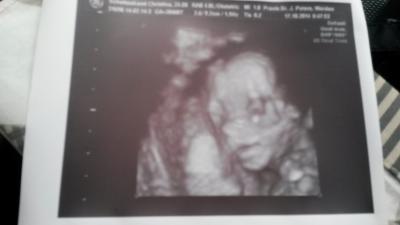

Liebe Mitschwangeren, Bei der Vorsorge war alles okay :) die kleine Maus wiegt schon 370 gramm. :) Baby-Kino war sooo toll :) In zwei Wochen dürf ma zur Feindiagnostik, wegen meinem Hashimoto und familiärer Vorbelastung und ich muss alle 4 Wochen zum Urologen wegen meinem Nierenstau. Anbei noch ein kleines Foto von unserer süßen Maus in 4D vom Kopf :) Wir sind jetzt schon sooo stolz auf die kleine.

Bild zu vorsorgeuntersuchung vom Freitag - Forum für März - Mamis